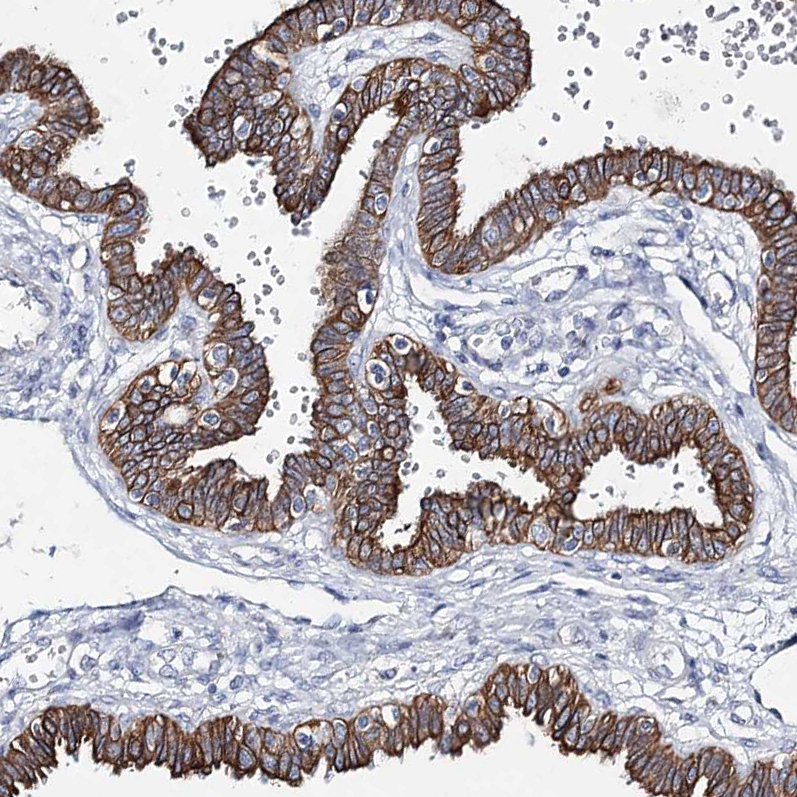

Immunohistochemical staining of human Fallopian tube shows strong membranous positivity in glandular cells.